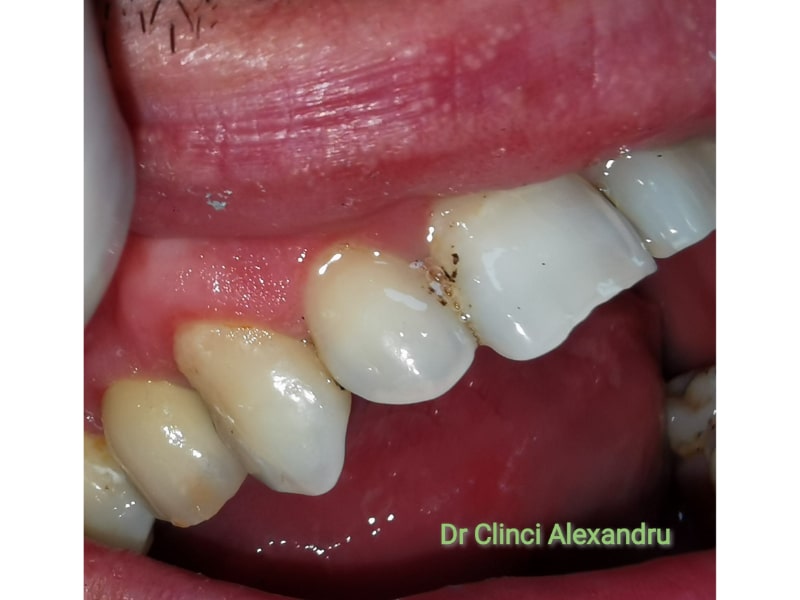

Zirconiu Multilayer